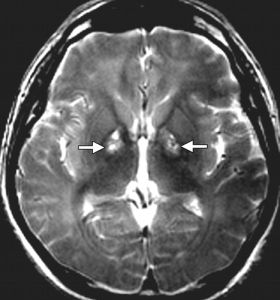

蒼白球是位於大腦兩側半球深部的基底核的重要組成部分。基底核由尾狀核、蒼白球、殼組成。其中蒼白球和殼又被合稱為豆狀核。

圖基底核是錐體外系的中繼核。其接受大腦皮質、丘腦等處的神經衝動,並經蒼白球發出纖維至丘腦而與大腦皮質聯繫。蒼白球的下行纖維,通過紅核、黑質、網狀結構等影響脊髓下運動神經元。

一般來說,蒼白球的病變可出現肌張力增高、動作減少及靜止性震顫(如帕金森綜合徵)等症狀。

【概述】 【病因】 【病理】 【臨床表現】 【診斷】蒼白球黑質變性又叫Joseph病,是一種與鐵代謝異常有關的罕見...CT檢查可無明顯改變,磁共振檢查可有蒼白球萎縮和順磁物質(鐵質)沉積的低...蒼白球內嚴重的神經元缺失,代之以大量神經膠質細胞;黑質內神經元明顯減少,色澤...